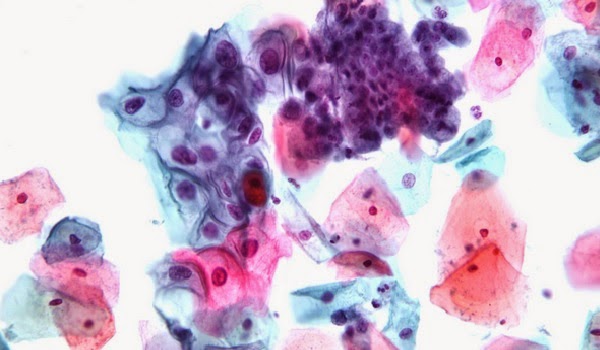

Molte donne sono restie a sottoporsi al pap test, questo serve a scovare l’eventuale presenza del papillomavirus (Hpv), una delle cause maggiori di sviluppo di tumori della cervice uterina. Secondo un gruppo di ricercatori guidati da Neha Pathak, della London School of Medicine, a breve l’esame delle urine potrà sostituire il pap test.

Lo studio pubblicato sulla rivista British Medical Journal, dimostra che questa analisi offre garanzie sufficienti nonostante sia meno efficace del test Hpv. In pratica i ricercatori basandosi su 14 ricerche precedenti e coinvolgendo oltre 1.443 donne, hanno dimostrato che il nuovo esame individua correttamente la presenza del virus nell’87 per cento dei casi positivi al test Hpv.

Henry Kitchener, ginecologo dell’Università di Manchester, spiega che: “Accanto a un’indifferenza crescente nei riguardi della prevenzione, osservata nelle giovani donne, è ben documentato che a costituire ostacoli allo screening sono anche difficoltà pratiche e fattori di tipo emozionale“. Sulla base di queste dichiarazioni i ricercatori sostengono che: “un esame non invasivo facilmente accessibile e accettabile per le donne, come la ricerca del papillomavirus nelle urine, potrebbe far aumentare l’aderenza allo screening“.